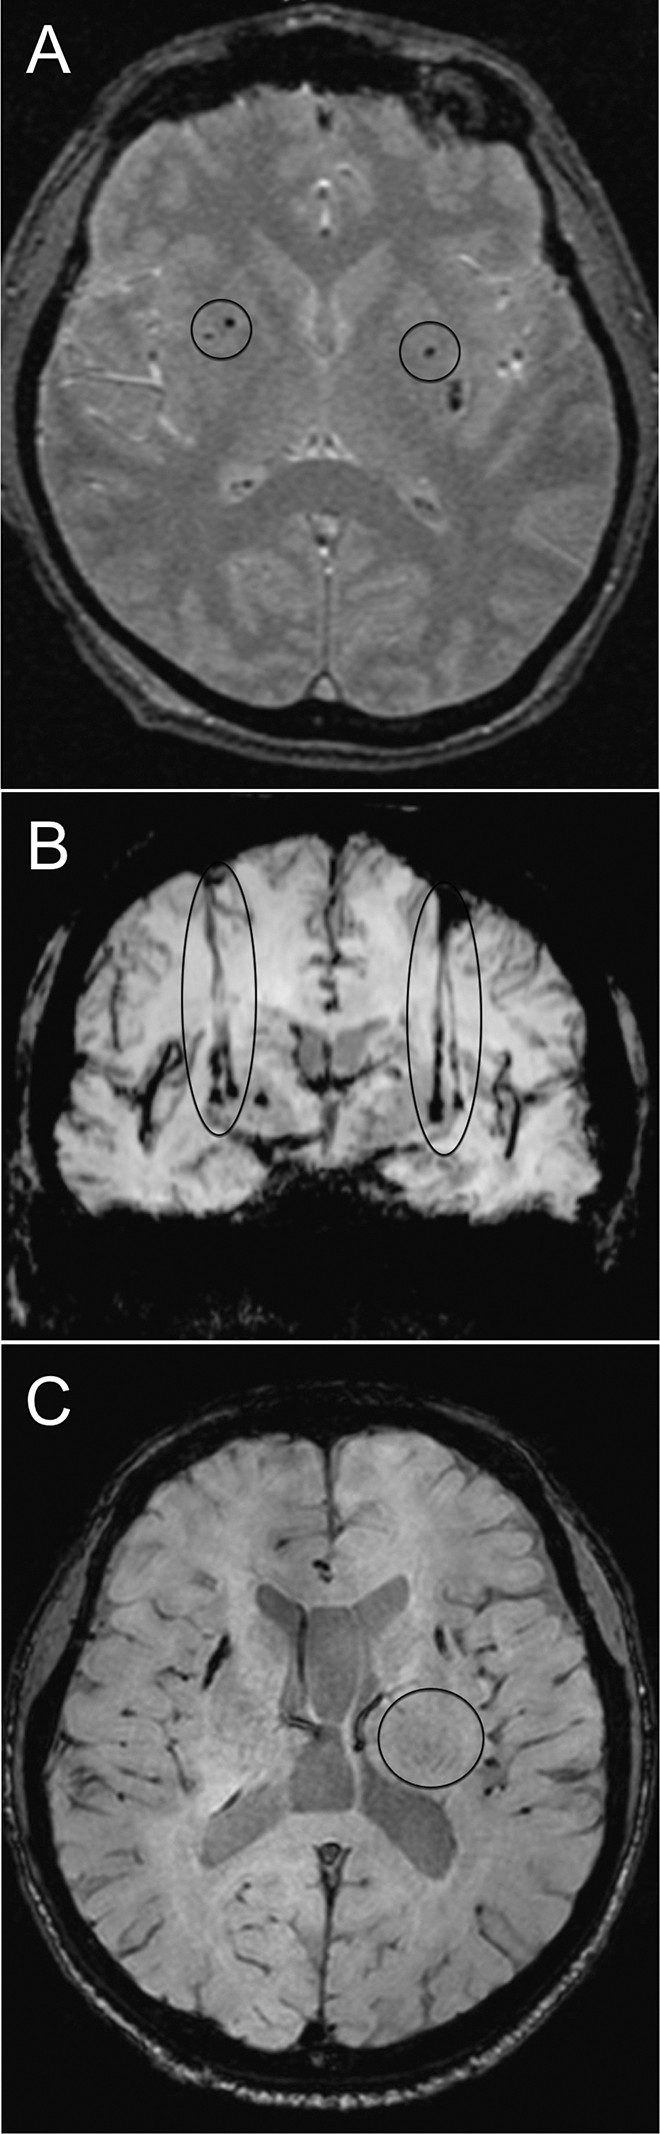

移植患者的代表性腦部 MR 圖像

如圖2所示。細(xì)胞植入的位點(diǎn)和軌跡路徑如圖 1 和 2 所示。分別參見(jiàn)圖 2A 和 2B。在1、2和4年隨訪的幾個(gè)針跡結(jié)束時(shí),在 T2 加權(quán)圖像上識(shí)別出小簇低信號(hào)。在 P4 的年度 MRI 監(jiān)測(cè)中,在右側(cè)殼核(圖2C)中觀察到強(qiáng)大的移植物生長(zhǎng),沒(méi)有大腦結(jié)構(gòu)的異常。未顯示腫瘤形成的證據(jù)。

圖2:移植患者的大腦MR圖像。